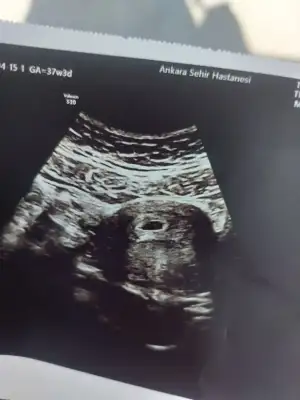

Sellaaam kızlar😍 6+3’ten selam doğumum 19 kasım 12 aralık görünüyor buraya katılmak istedimm bu da kesem kalp atışı için haftaya gidicem😍

Ya benim kesem biraz uamuk gibi geldi endişe ettim. Bende 30 nisanda kalp atışına gideceğim. Gittiğimde 7+2 olacağız